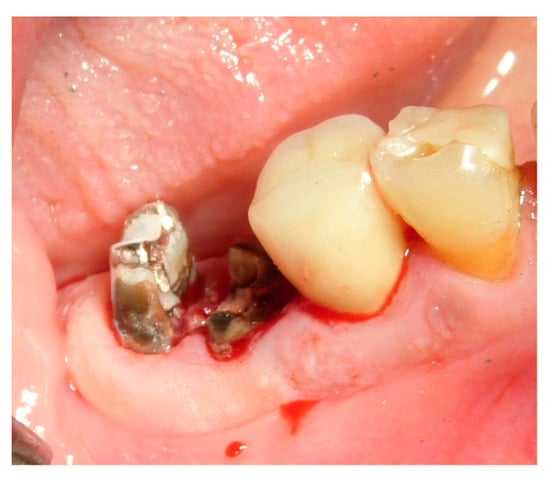

The vertical average defect was 9.16 mm, buccal lateral/palatal 7.0 mm, and mesio-distal 10.3 mm. The measurements were intraoperatively performed with a millimeter periodontal probe. The endodontic material mechanically cleaned before the tooth was placed inside the Tooth Transformer device. The endodontic material was removed using a drill bur with the attention to cut the canal in excess with the aim to remove all the cement. No surgical complications were registered. Pre and post-operative X-rays (section from CBCT) were collected from the same case (Figure 1, Figure 2, Figure 3 and Figure 4). After four months, 13 histological and histomorphometrical evaluations were performed (Figure 5). The Bone Volume/Total Volume average (BV%) was 41.47 (S.D. ± 11.51), the Residual Graft/Total Volume average (Graft%) was 16.60 (S.D. ± 7.09), and the Vital Bone/Total Bone average (VB%) was 21.89 (S.D. ± 9.72). No extraneous material (gutta-percha or cement) was detected in all samples (Table 3).

Figure 7. Dental element 46 to be extracted with the need for ridge maintenance due to an extensive interradicular defect.